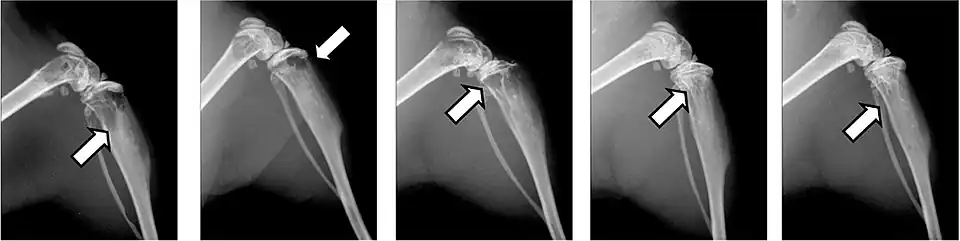

Fractures pathologiques

La fracture pathologique est une circonstance rare de découverte d'une métastase osseuse[75],[76].

Les fractures pathologiques sont des fractures de l’os qui surviennent sans atteinte extérieure, à cause d'un affaiblissement pathologique de la matrice osseuse. Les métastases surtout ostéolytiques, mais aussi parfois ostéocondensantes, affaiblissent l’os concerné qui selon les circonstances peut être sursollicité par des contraintes mécaniques faibles, et rompt. Ces fractures peuvent survenir dans des situations de tous les jours, comme le fait de se lever d'un siège ou de déplacer le patient[77]. Pour les métastases ostéocondensantes, l'épaisseur de l’os est certes augmentée, mais sa solidité est abaissée par sa construction complètement non structurée[6]. Dans le domaine de la colonne vertébrale, elles peuvent conduire à des enraidissements[65].

Les fractures pathologiques conduisent à des complications étendues et ont une influence considérable sur la qualité de vie et sur le pronostic. La durée de survie moyenne peut être diminuée de plusieurs mois[22]. Les bisphosphonates peuvent éviter dans bien des cas cette forme de fracture[78],[79].

Ce sont la plupart du temps les côtes ou les corps vertébraux qui sont atteints par les fractures. Les fractures dans les os longs, en particulier au col du fémur, présentent une gravité particulièrement élevée et sont le principal motif pour une intervention chirurgicale. Les fractures des corps vertébraux peuvent conduire à des syndromes de compression médullaire[65].

- Vues de fractures pathologiques

Fracture pathologique de l'humérus sur une métastase de carcinome du rein

Fracture pathologique du bras gauche sur une métastase osseuse de cancer du sein

Scintigraphie corps entier avec 99mTc-HDP de la patiente avec une fracture du bras due à une métastase du cancer du sein